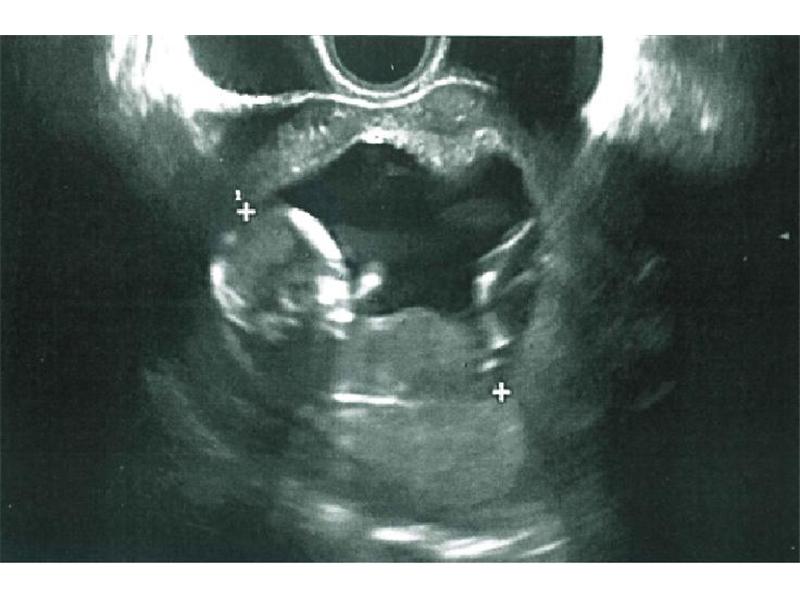

Bobíšek v bříšku